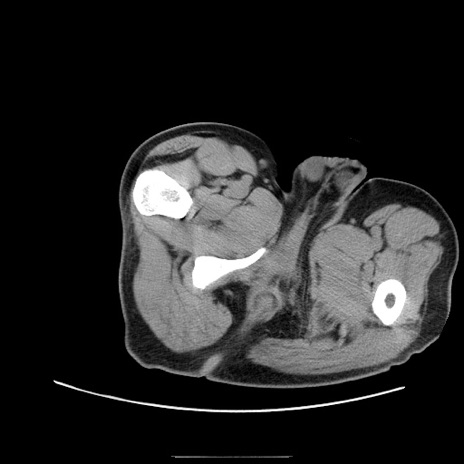

症例22(横断像)

【症例】50歳代男性

【主訴】腹痛

【現病歴】AVMからの被殻出血のため回復期リハ病棟入院中。 本日午後3時頃急に下腹部痛が出現した。

【既往歴】AVM、被殻出血、虫垂炎、高血圧

【身体所見】意識晴明、左半身不全麻痺、会話の理解は良好、36.5°C、腹部:膨隆、全体に板状硬、下腹部正中に圧痛点あり、反跳痛-、筋性防御不明、右下腹部にope scar

【データ】WBC 9400、CRP 0.06